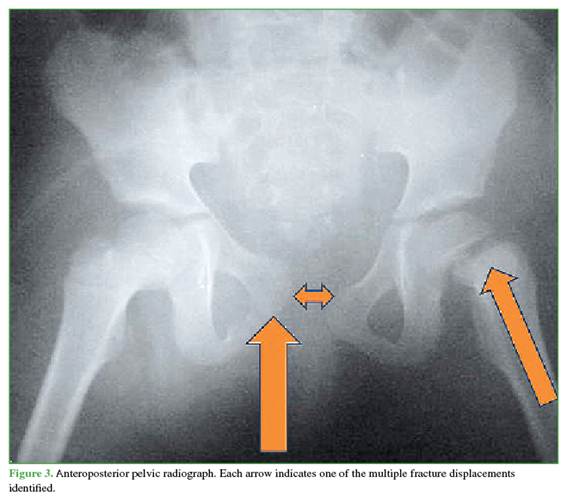

Of all the radiographs obtained, the AP pelvic radiograph revealed fractures consistent with polytrauma (Figure 1). A type C pelvic fracture according to the AO classification was observed, along with an avulsion of the iliac wing and a type A fracture within the same classification.1 In the left proximal femoral epiphysis, a type I (transepiphyseal) epiphysiolysis was identified according to the Delbet classification (Figures 2 and 3). 2